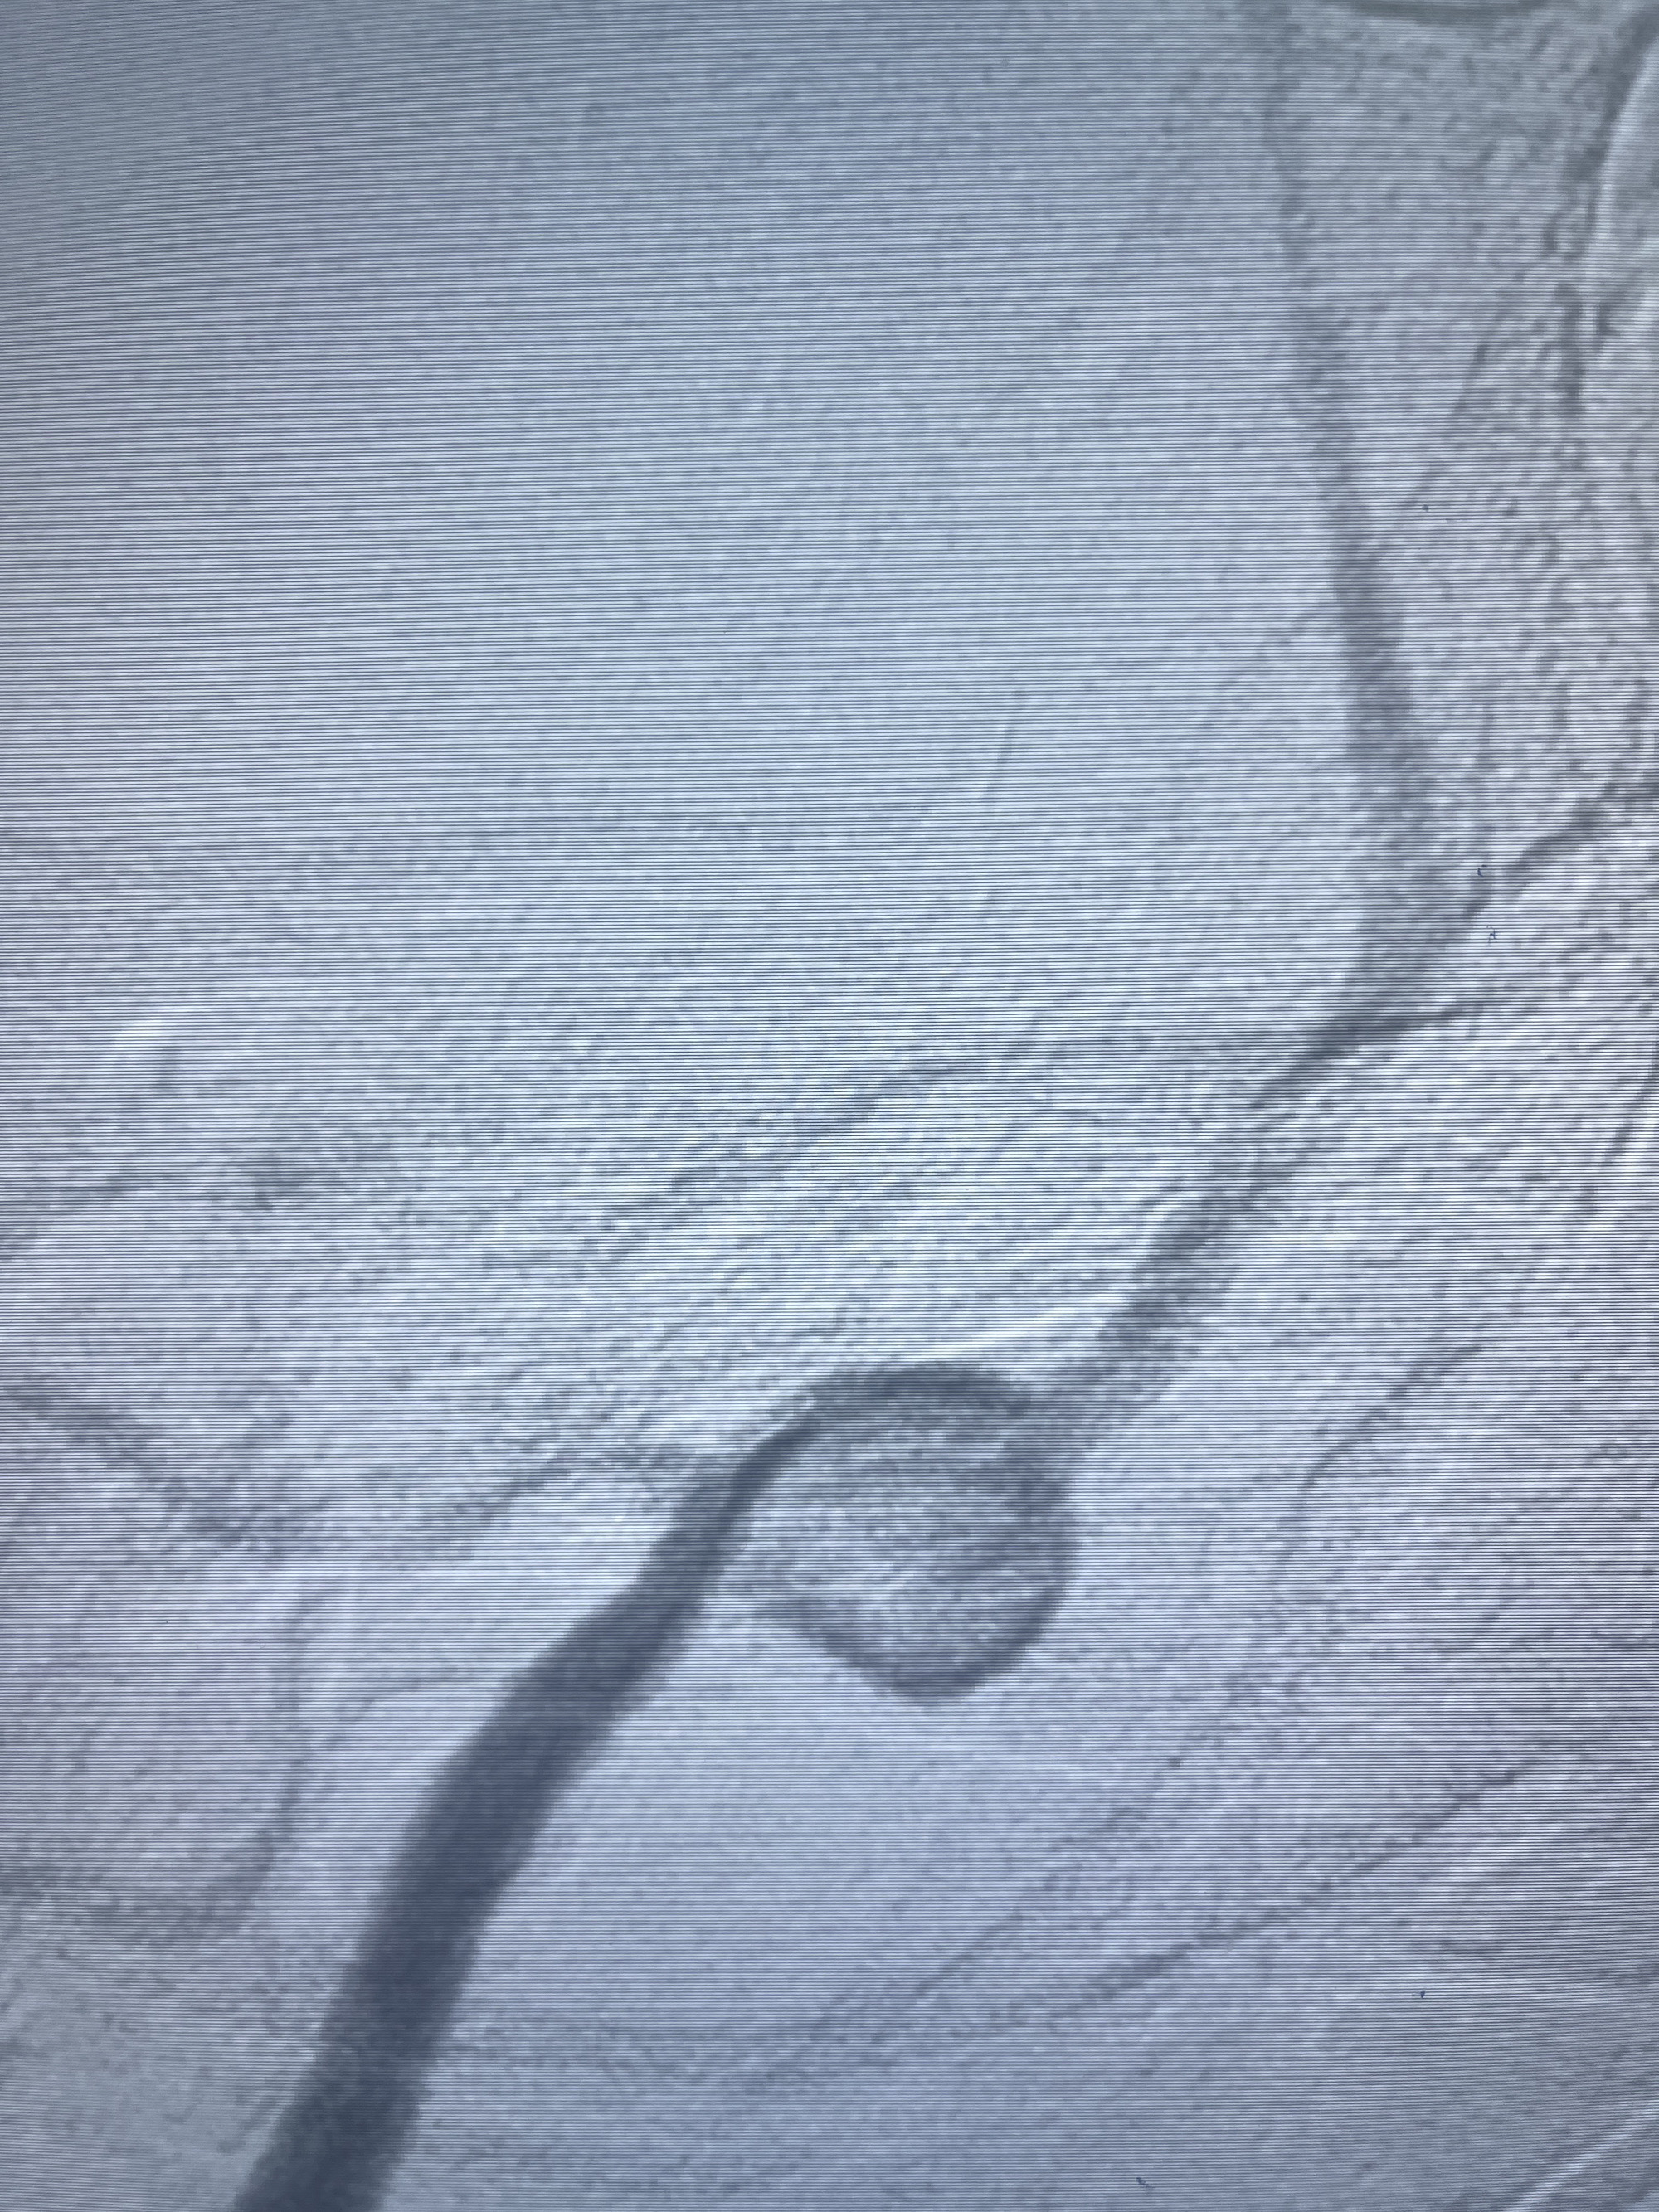

202.04.28脑血管造影:右侧大脑后动脉远段闭塞,右侧椎动脉V4段可见“囊状造影剂填充影”,大小7.64*7.65mm,可见PICA由动脉瘤发出;